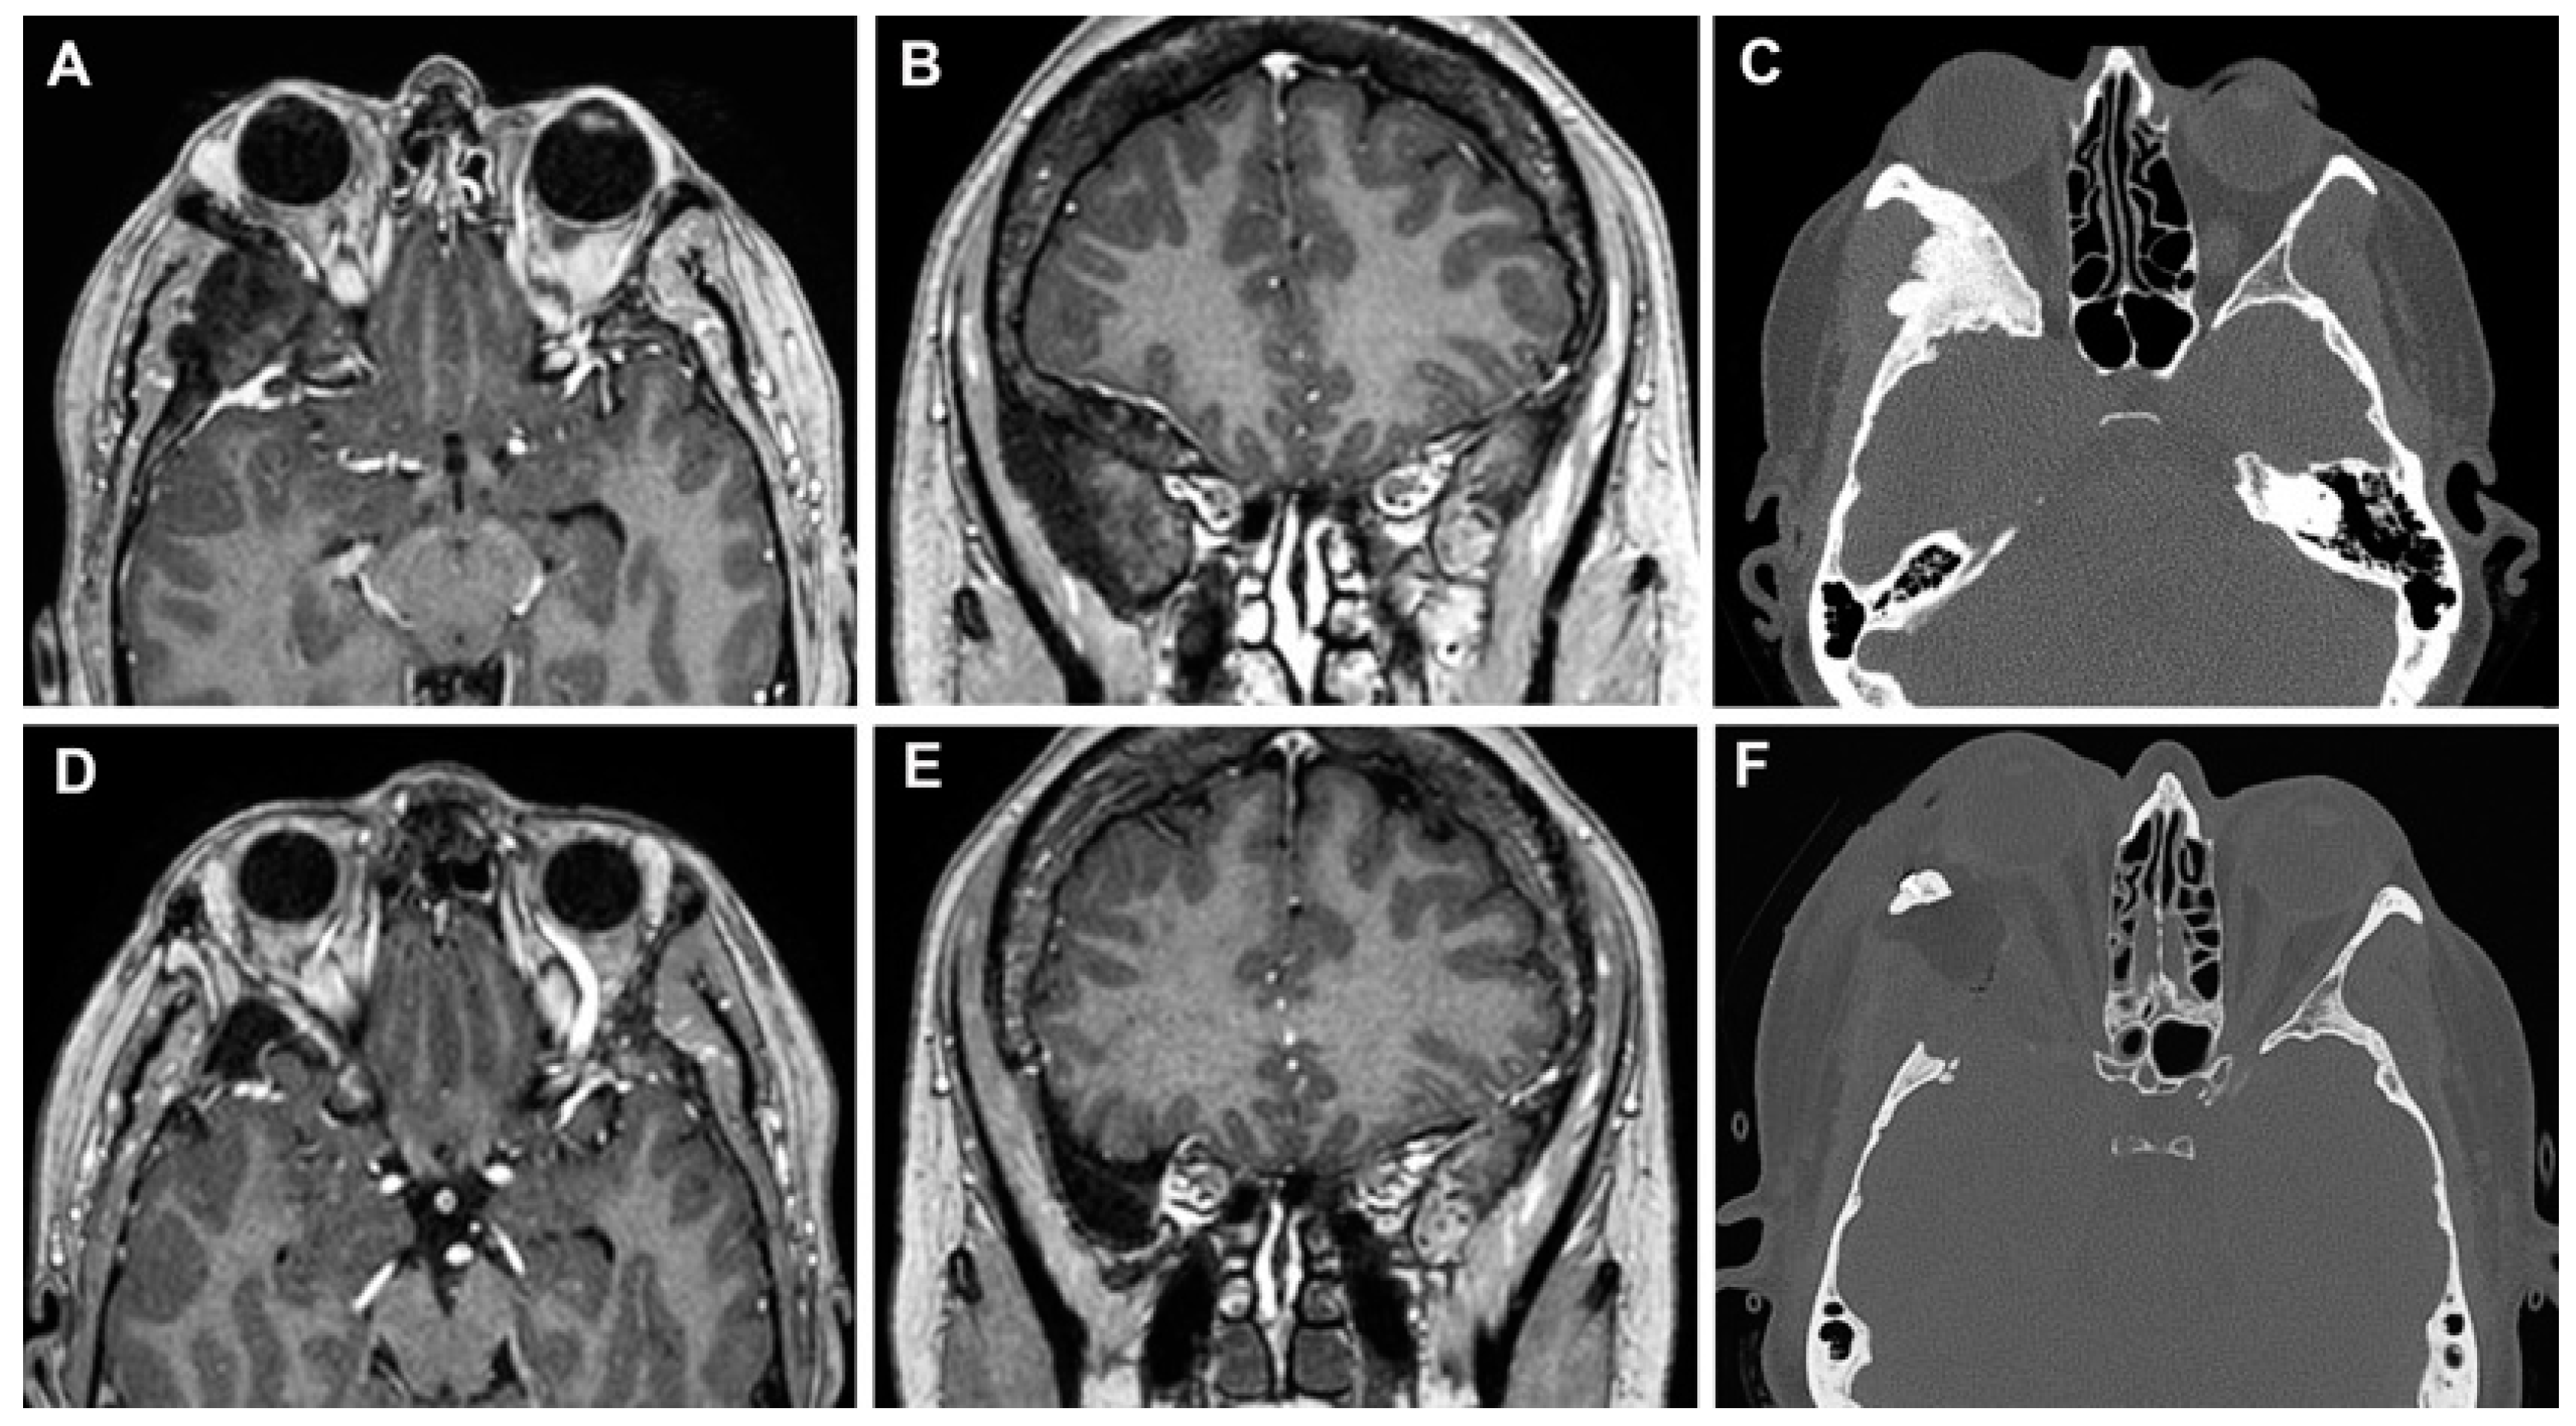

3.3.1. Case 1